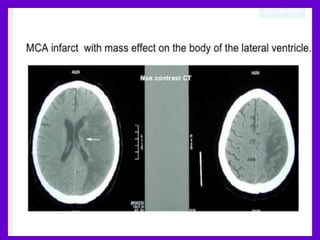

• MCA infarction: on CT an

area of hypo attenuation

appearing within six

hours is highly specific

for irreversible ischemic

brain damage

Obscuration lentiform nucleus

Axial unenhanced CT image

shows hypo attenuation and

obscuration of the left

lentiform nucleus (arrows),

which, because of acute

ischemia in the lenticulostriate

distribution, appears

abnormal in comparison with

the right lentiform nucleus.